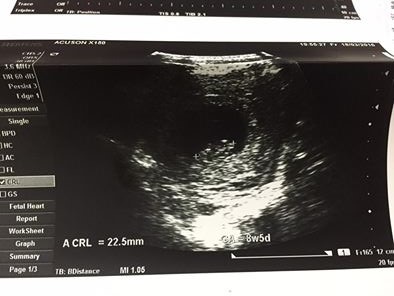

醫生說沒有現在看起來很好也長到了2.5公分~

↑ 獲得了葉黃素的第一張超音波照片!!!(想必不是媽媽的人根本看不懂他在哪哈哈ㄏ)